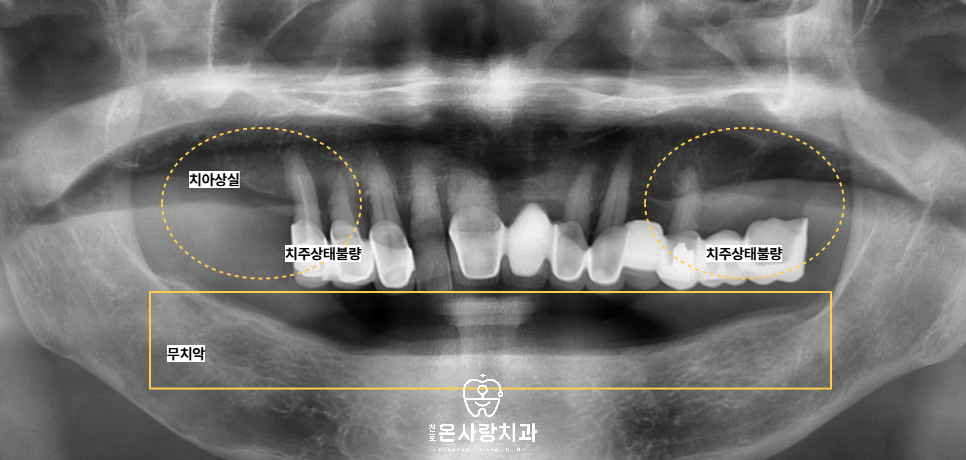

이번 환자분의 경우 아래쪽은

완전 무치악 상태로

아래쪽에는 전체 임플란트

식립을 계획하였습니다.

위쪽은 오른쪽 위의

어금니부위를 제외한

대부분의 치아가 남아 있었지만,

전반적인 치조골 흡수와 염증이 심해서

치주상태가 불량한 보철이 되어있는

치아는 모두 발치가 필요했습니다.

다만 전치부는 잇몸 상태와

치근 길이가 양호하여

신경치료 후 크라운을 씌워

가능한 살리기로 하였습니다.